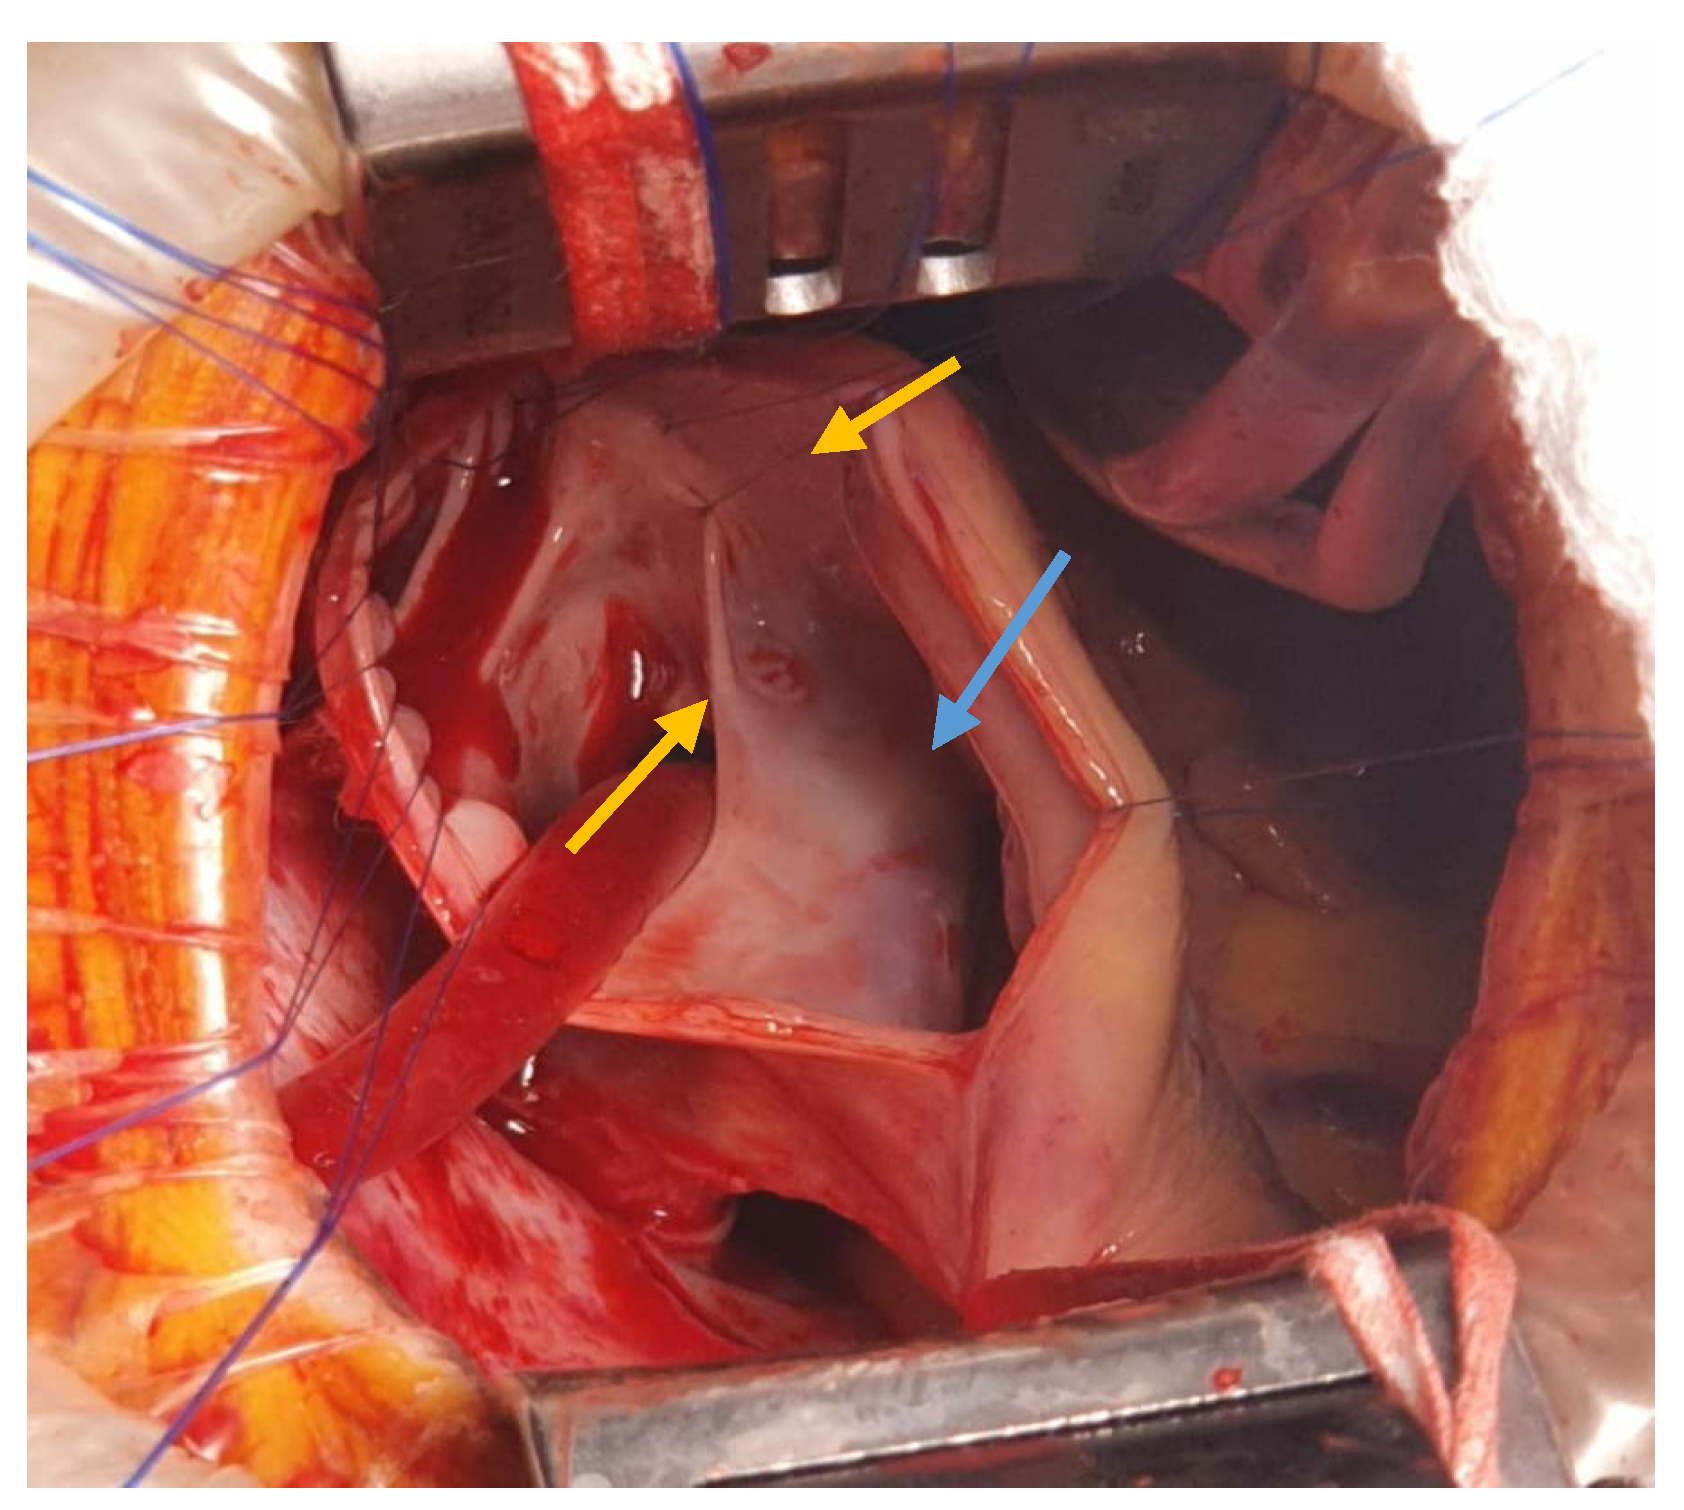

The interatrial defect was exposed through a right atriotomy extended across the cavoatrial junction into the superior vena cava. The examination of the right atrium cavity revealed an atrial septal defect in the proximity of the SVC and both right pulmonary veins draining into the SVC, proximally (Figure 3 and Figure 4).

Figure 3. View of PAPVD in the SVC (pulmonary veins in the SVC—yellow arrow).

Figure 4. Intra-atrial look of the SV-ASD with PAPVD (pulmonary veins ostia—yellow arrows; ASD—blue arrow).